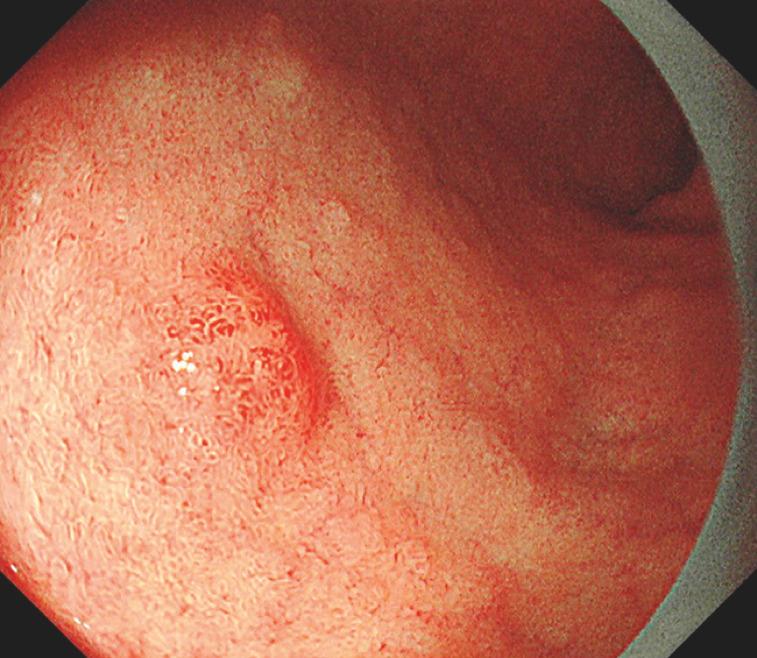

Misidentification of a duodenal neuroendocrine tumor as an adenoma, with subsequent attempted resection by cold snare polypectomy.